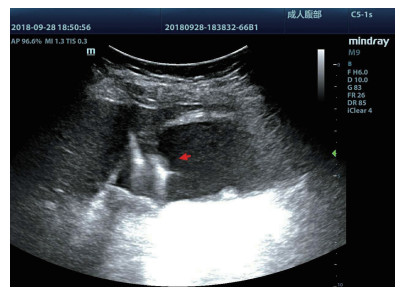

1.3 手术过程 1.3.1术前经肘静脉超声造影:行PTGBD前半h经肘静脉快速团注SonoVuel 5 mL,在对比脉冲序列造影成像模式下进行观察,根据不同组织造影剂凝聚的时间及浓度差异,判断胆囊周围组织黏连程度、胆囊壁完整程度(图 1),如出现胆囊壁造影剂充盈缺损(图 2、3),则考虑胆囊壁坏死或穿孔,根据静脉造影情况选择合适的置管入路,避开胆囊穿孔的部位及黏连组织。

| 图 1 经肘静脉超声造影胆囊图像,造影图(左),二维超声图(右) |